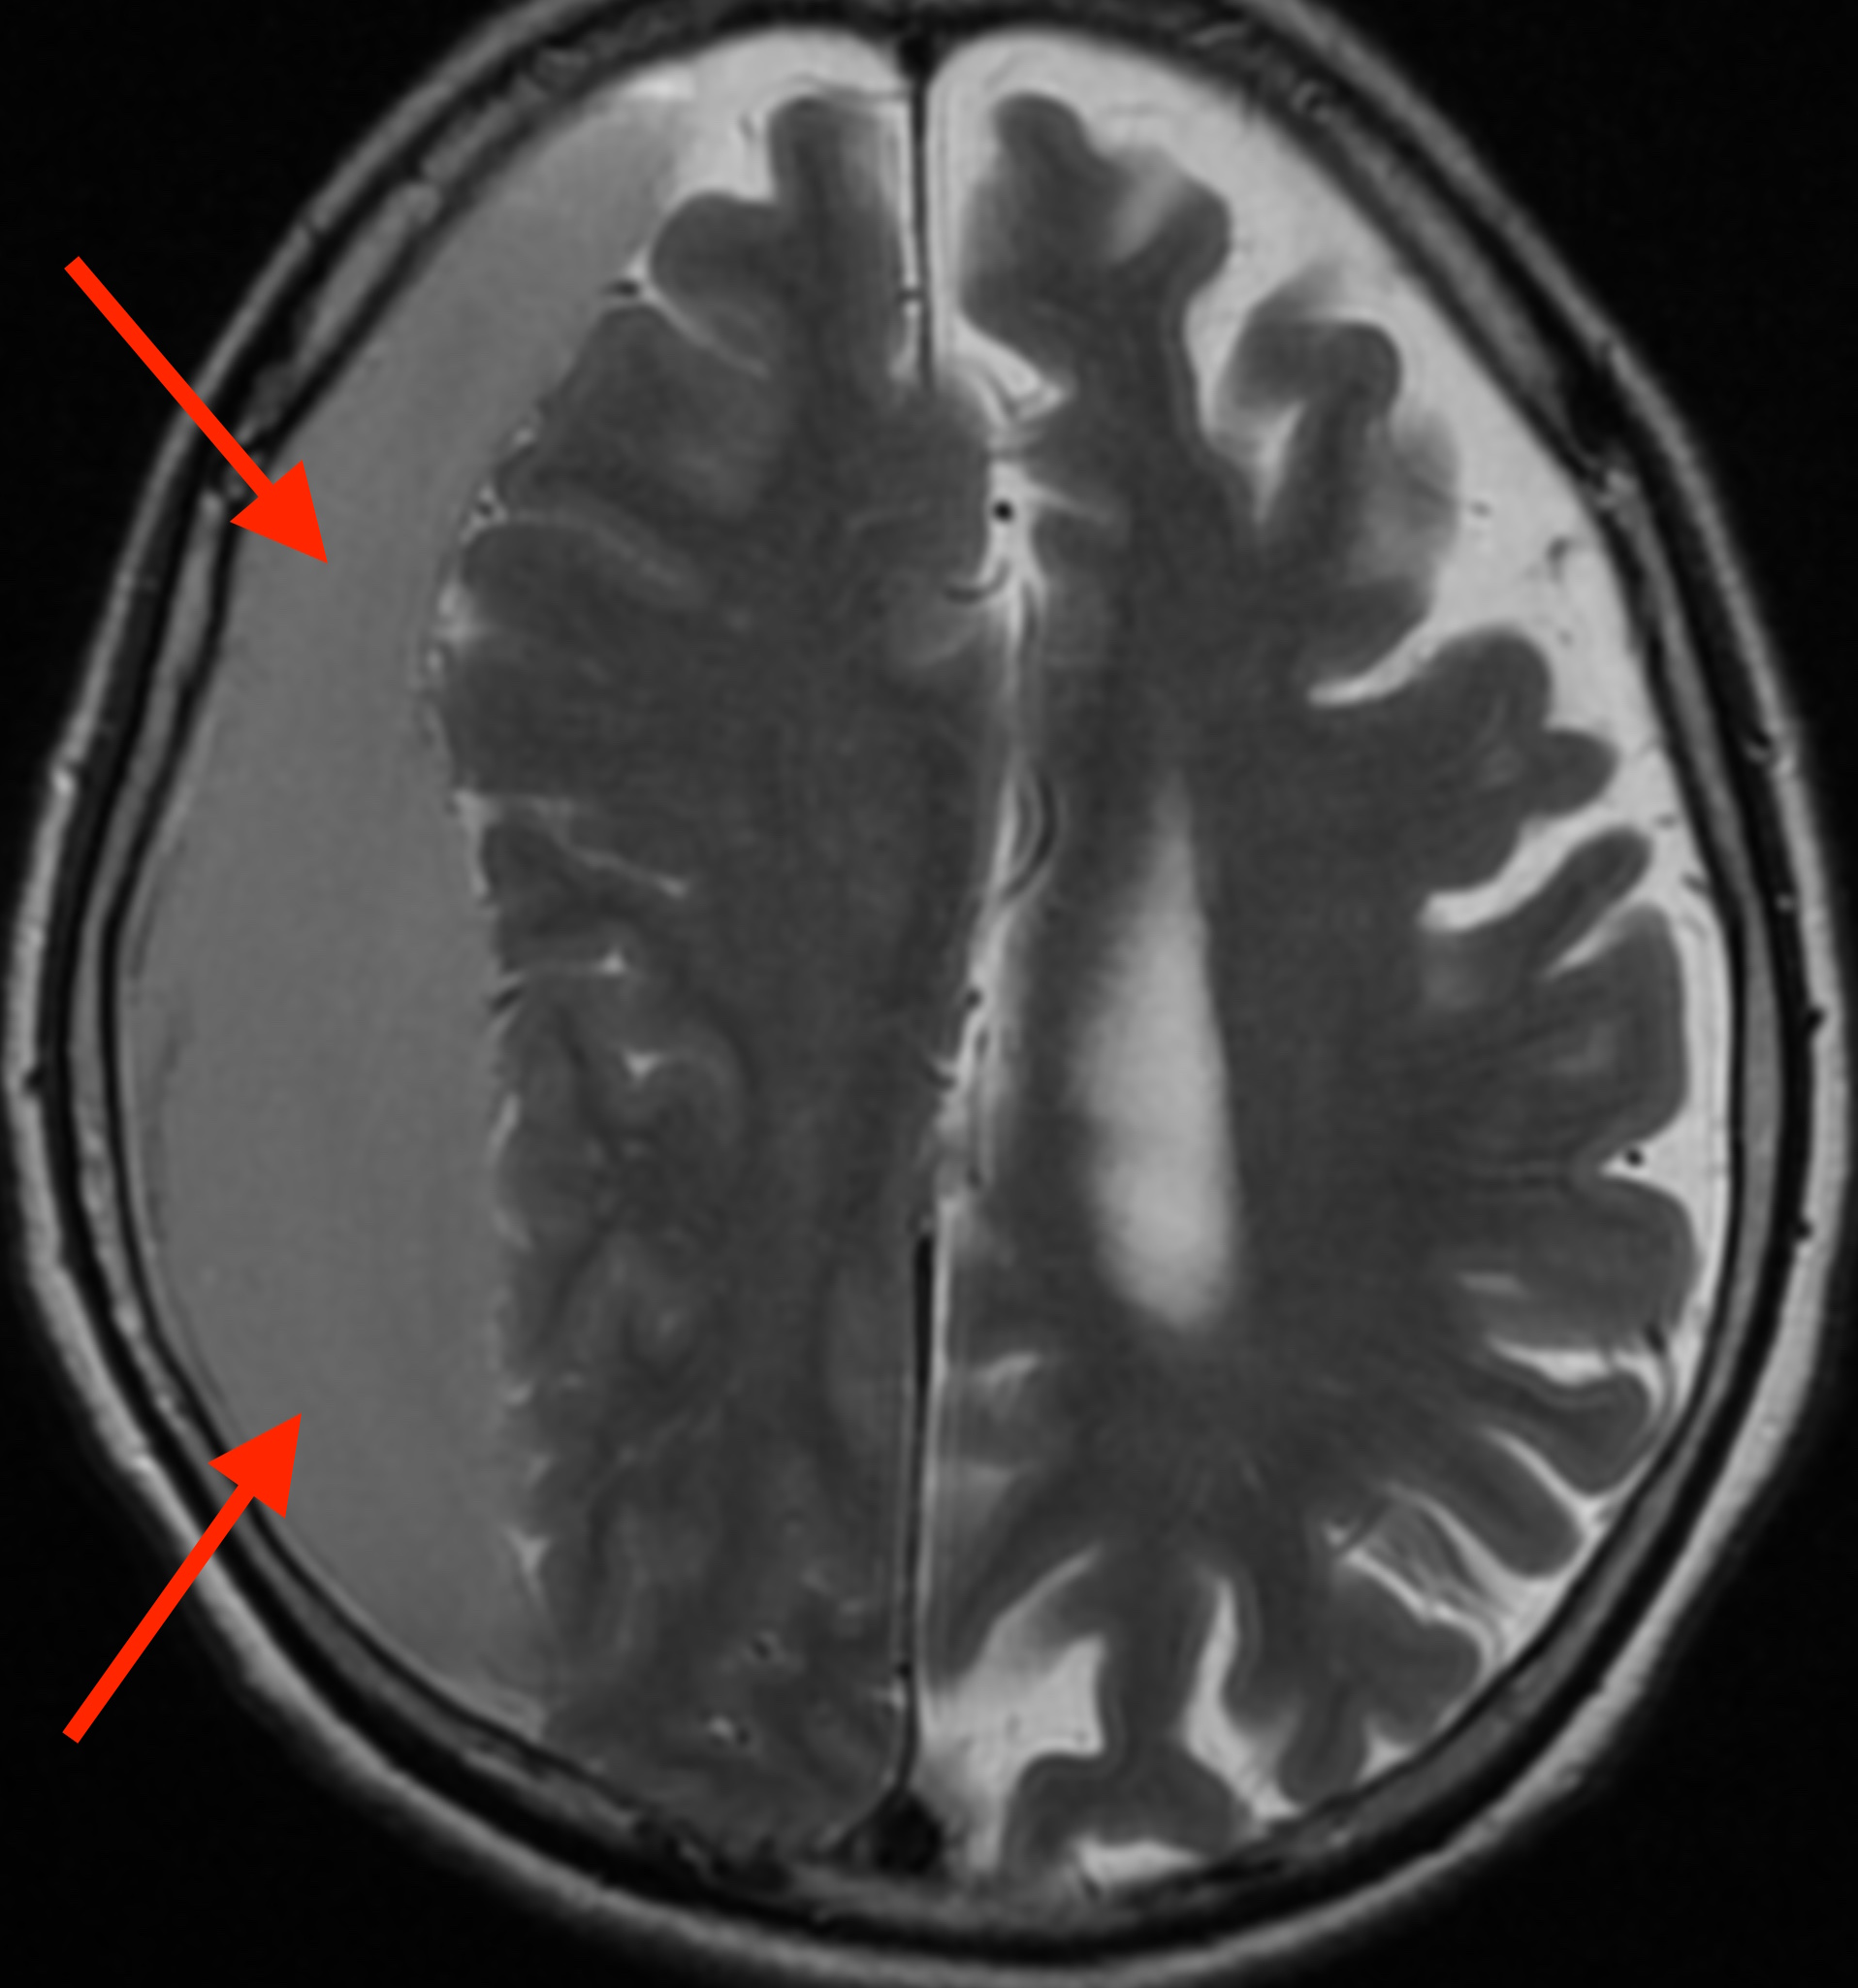

MRI検査をしたところ、

脳の右側に血液が貯まっていて脳を圧迫しており、慢性硬膜下血腫2) という状態です。

慢性硬膜下血腫とは、頭蓋骨の内側にある硬膜という固い膜の静脈が破れて出血した状態で、強く頭をぶつけた後に生じる事が多いですが、原因がはっきりしない場合もあります。頭をぶつけた後、1ヶ月以上たってから生じる事もあります。